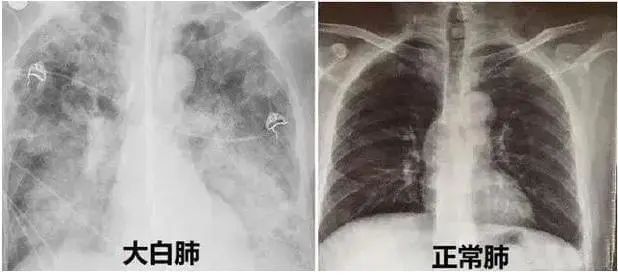

新冠后的“白肺”焦慮,如何早診斷早治療?

近期,多地醫(yī)生發(fā)現(xiàn)患者出現(xiàn)肺炎或白肺癥狀,引發(fā)關注。那么什么是白肺呢?其實白肺是肺部影像學表現(xiàn)的一個口語化描述。當出現(xiàn)炎癥和感染,肺泡被滲出液等填充,在影像學上的表現(xiàn)就是出現(xiàn)白色區(qū)域。并不是只要肺部出現(xiàn)了炎癥就都叫白肺,一般來講肺部炎癥較重、滲出液較多,白色的影像區(qū)域面積達到70%?80%時,在臨床上把它稱為白肺。通過“啄醫(yī)生”可以準確地識別新冠肺炎的典型白肺影像,以下選取幾例最新病例加以說明。

案例一,61歲,女性,確診病例

胸片顯示整個雙肺已經(jīng)白化